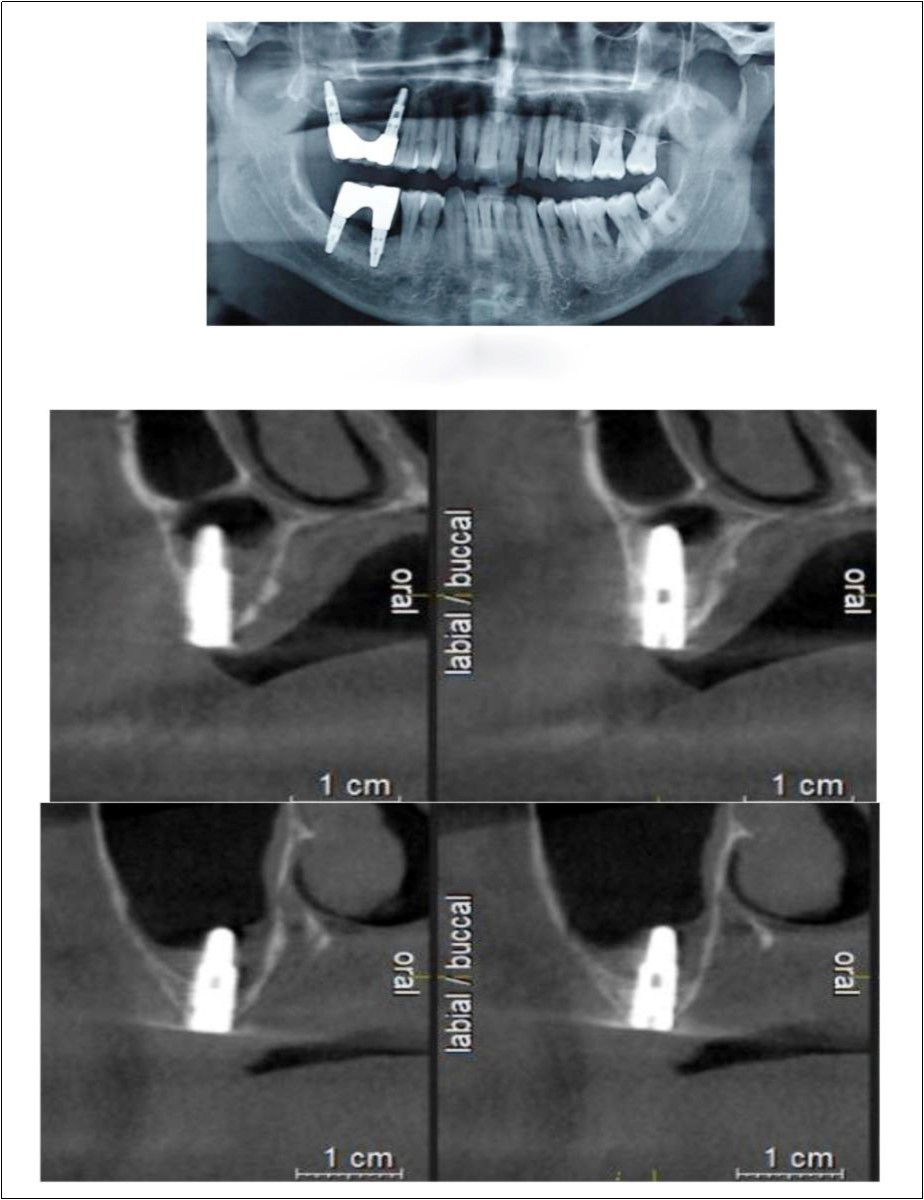

Sinus augmentation procedures were carried-out in 17 patients seeking implant options for oral rehabilitation including 10 for direct and 10 of indirect procedures (n=20, 10 direct and 10 indirect). The study comprised of 43% females and 57% males with a mean age of 46.07 years. A total of 17 patients (20 segments) satisfying the above criteria requiring placement of implants in atrophic maxilla/ increased pneumatisation of the maxillary sinus were selected for the study. The patients were informed about the study including the use of the synthetic graft material and their approval was sought before their inclusion in the study. A written informed consent was obtained from each of the participating patients. For each patient, a detailed case history was taken including chief complaint, history of presenting illness and medical history and personal history. A thorough clinical examination, including systemic and regional examination, was done. Patients with sinus pathology, previous sinus surgeries, chronic smokers, patients under 18 years of age, and with underlying systemic conditions which contradicts any surgical procedures were excluded from the study. The type of sinus lift was decided based on the pre-operative residual bone height evaluated radiographically. The residual bone height was recorded using CBCT scan and a computer based software where the measurements were made from the crest of the ridge till the sinus floor lining. Indirect sinus augmentation was done in patients with a bone height of <9mm but more than or equal to 5mm. Patients with a bone height of less than 5mm were taken up for direct sinus augmentation. The period of edentulousness varied from 6 months to 12 months. Apically tapered, commercially pure titanium implants (Life Care Devices Private Limited Mahim, West Mumbai, India) were used for patients undergoing indirect sinus augmentation. The length of implant was 8, 10, and 11.5 with diameters of 3.5, 4.0, and 5 mm respectively. Patients in the category of direct augmentation underwent the lateral approach procedure and augmentation with an alloplastic graft material. Implant placement was done after 6 months as the second stage procedure. The patients were assessed clinically at immediate post-operatively, and at 1 week, 1 month, 3 months, and 6 months post-operatively. Radiographic assessment for bone height was done pre-operatively and at 6 months post-operatively using cone beam computer tomography. In this comparative study, the measurements were tabulated and statistically analyzed to evaluate the difference in increase in bone height between direct and indirect sinus augmentation procedures radiographically. Orthopantomographs (screening tool) were taken to rule-out other pathologies and as a part of initial assessment. CBCT scans were assessed for pre-operative and post-operative bone height, bone width and bone density. The CBCT scans were obtained from Kodak 9300 which is a hybrid machine using a CS3D imaging software and flap panel detector sensor with exposure parameters of 90 KVp and 10 mA and resolution of 90 microns. The cross sections were made 1mm apart. (Image 1, Image 2, Image 3) The bone height measured pre-operatively using CBCT considered the pre-operative bone height as a measurement taken from the crest of the ridge till the sinus floor and post-operatively, from the crest till hyper-density evident apically. These measurements were standardized as a computer software drawing tool was used. Bone width was taken as the bucco-palatal width at three intervals- at the crest, 3mm from the crest and 6mm from the crest. Bone density was assessed visually by the width of trabecular pattern and were classified based on Misch‘s classification.4 Another additional bone density tool used was the pixel values (the gray scale values) obtained on the CBCT scan, although not reliable, and comparison done pre-operatively and post-operatively. The pixel values contained were a mean of three measurements obtained along the residual bone corresponding with the bone width levels.

With a pre-operative residual bone height of 0.8 mm in 16 region and 1.5 mm in 17 region, direct sinus augmentation was carried-out in a 40 year old male patient followed by implant placement of 3.75 x 11.5 dimensions as a single step procedure. Lateral window was created and synthetic graft material was dispensed through the lateral osteotomy site to maintain the elevated sinus membrane followed by placement of two dental implants through the crestal approach measuring 3.75 x 11.5 mm under local anesthesia and strict aseptic protocols. At the end of 6 months, a CBCT scan was advised to evaluate the increase in bone height which was 11 mm and 10.8 mm in 16 and 17 region respectively. (Figure 1, Figure 2)

Figure 1.Pre-operative Orthopantomograph and cross sections of CBCT showing residual alveolar bone height

Figure 2.Post-operative Orthopantomograph and cross sections of CBCT showing an increase in residual alveolar bone height